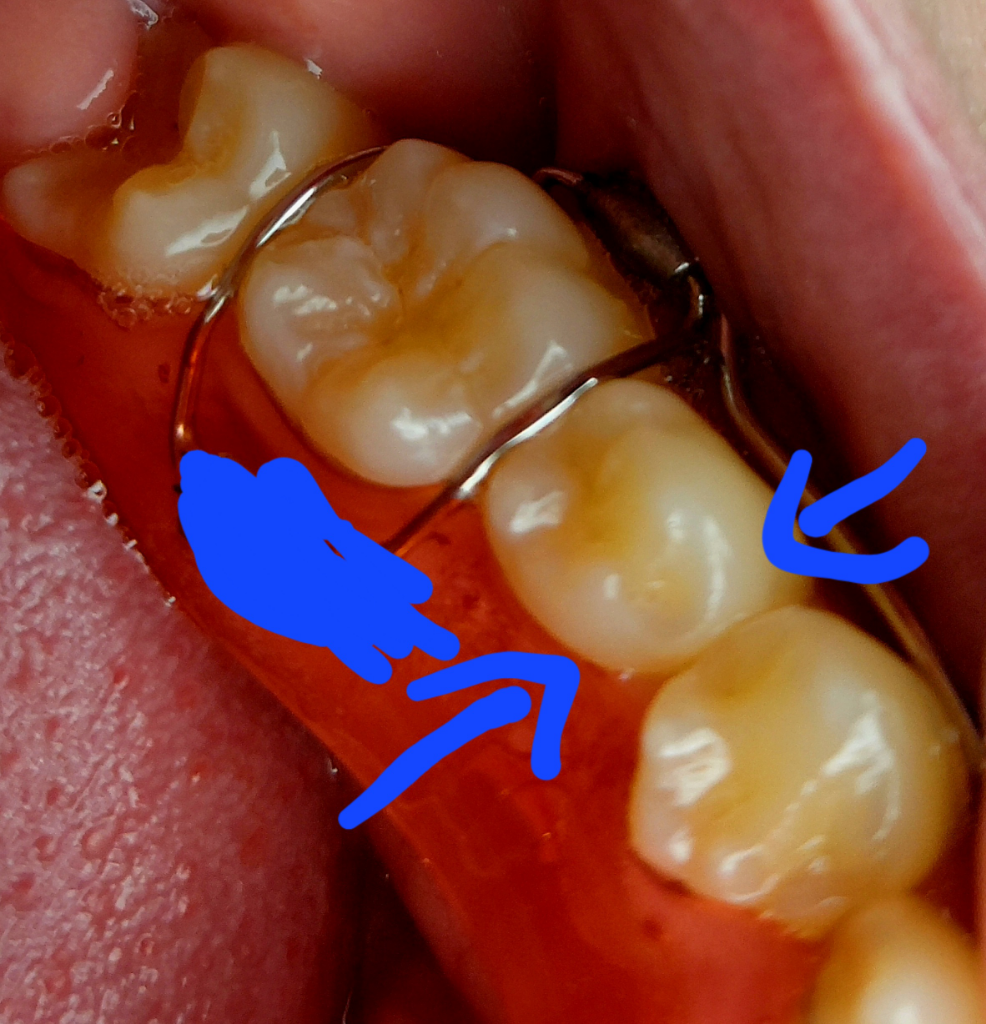

사진으로 보면 치아가 갈리거나 그런건 없어 보입니다. 크게 문제가 잇는건 아닌거 같으니 걱정하지 않으셔도 될것같습니다.

사진으로는 큰 문제가 없어보이며 유지장치를 오래 사용안하다가 꼈을 경우에는 치아에 이물감이 느꺼질수 있습니다

대부분 시간이 지나면서 괞찮아 지는데 1주일 이상 지속된다면 치과에서 진료를 받아보세요

사진상으로는 특별히 이상이 보이지는 않습니다.

유지장치가 잘안맞다면 교정치과를 가보시는게 좋겠습니다